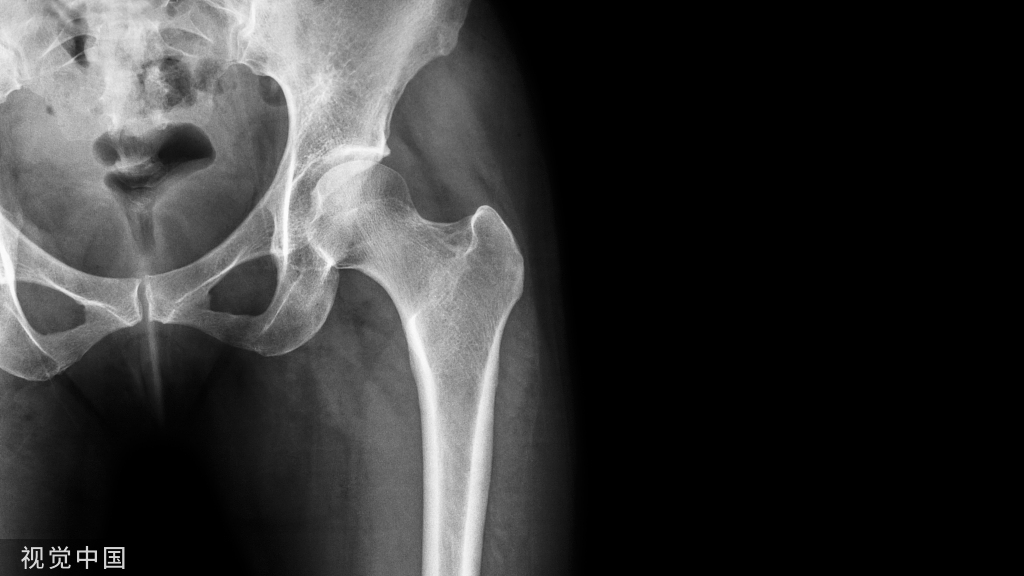

附病例(X线+CT):

病人女性,外伤后骶尾部疼痛,dr片示骶尾关节对应关系差,骶5椎体欠规则。ct重建示骶5椎体粉碎性骨折!

X线: